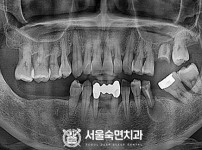

임플란트-전후사진2

치과를-선택할-때-꼭-확인하세요-서울숙면치과-임플란트-전후사진